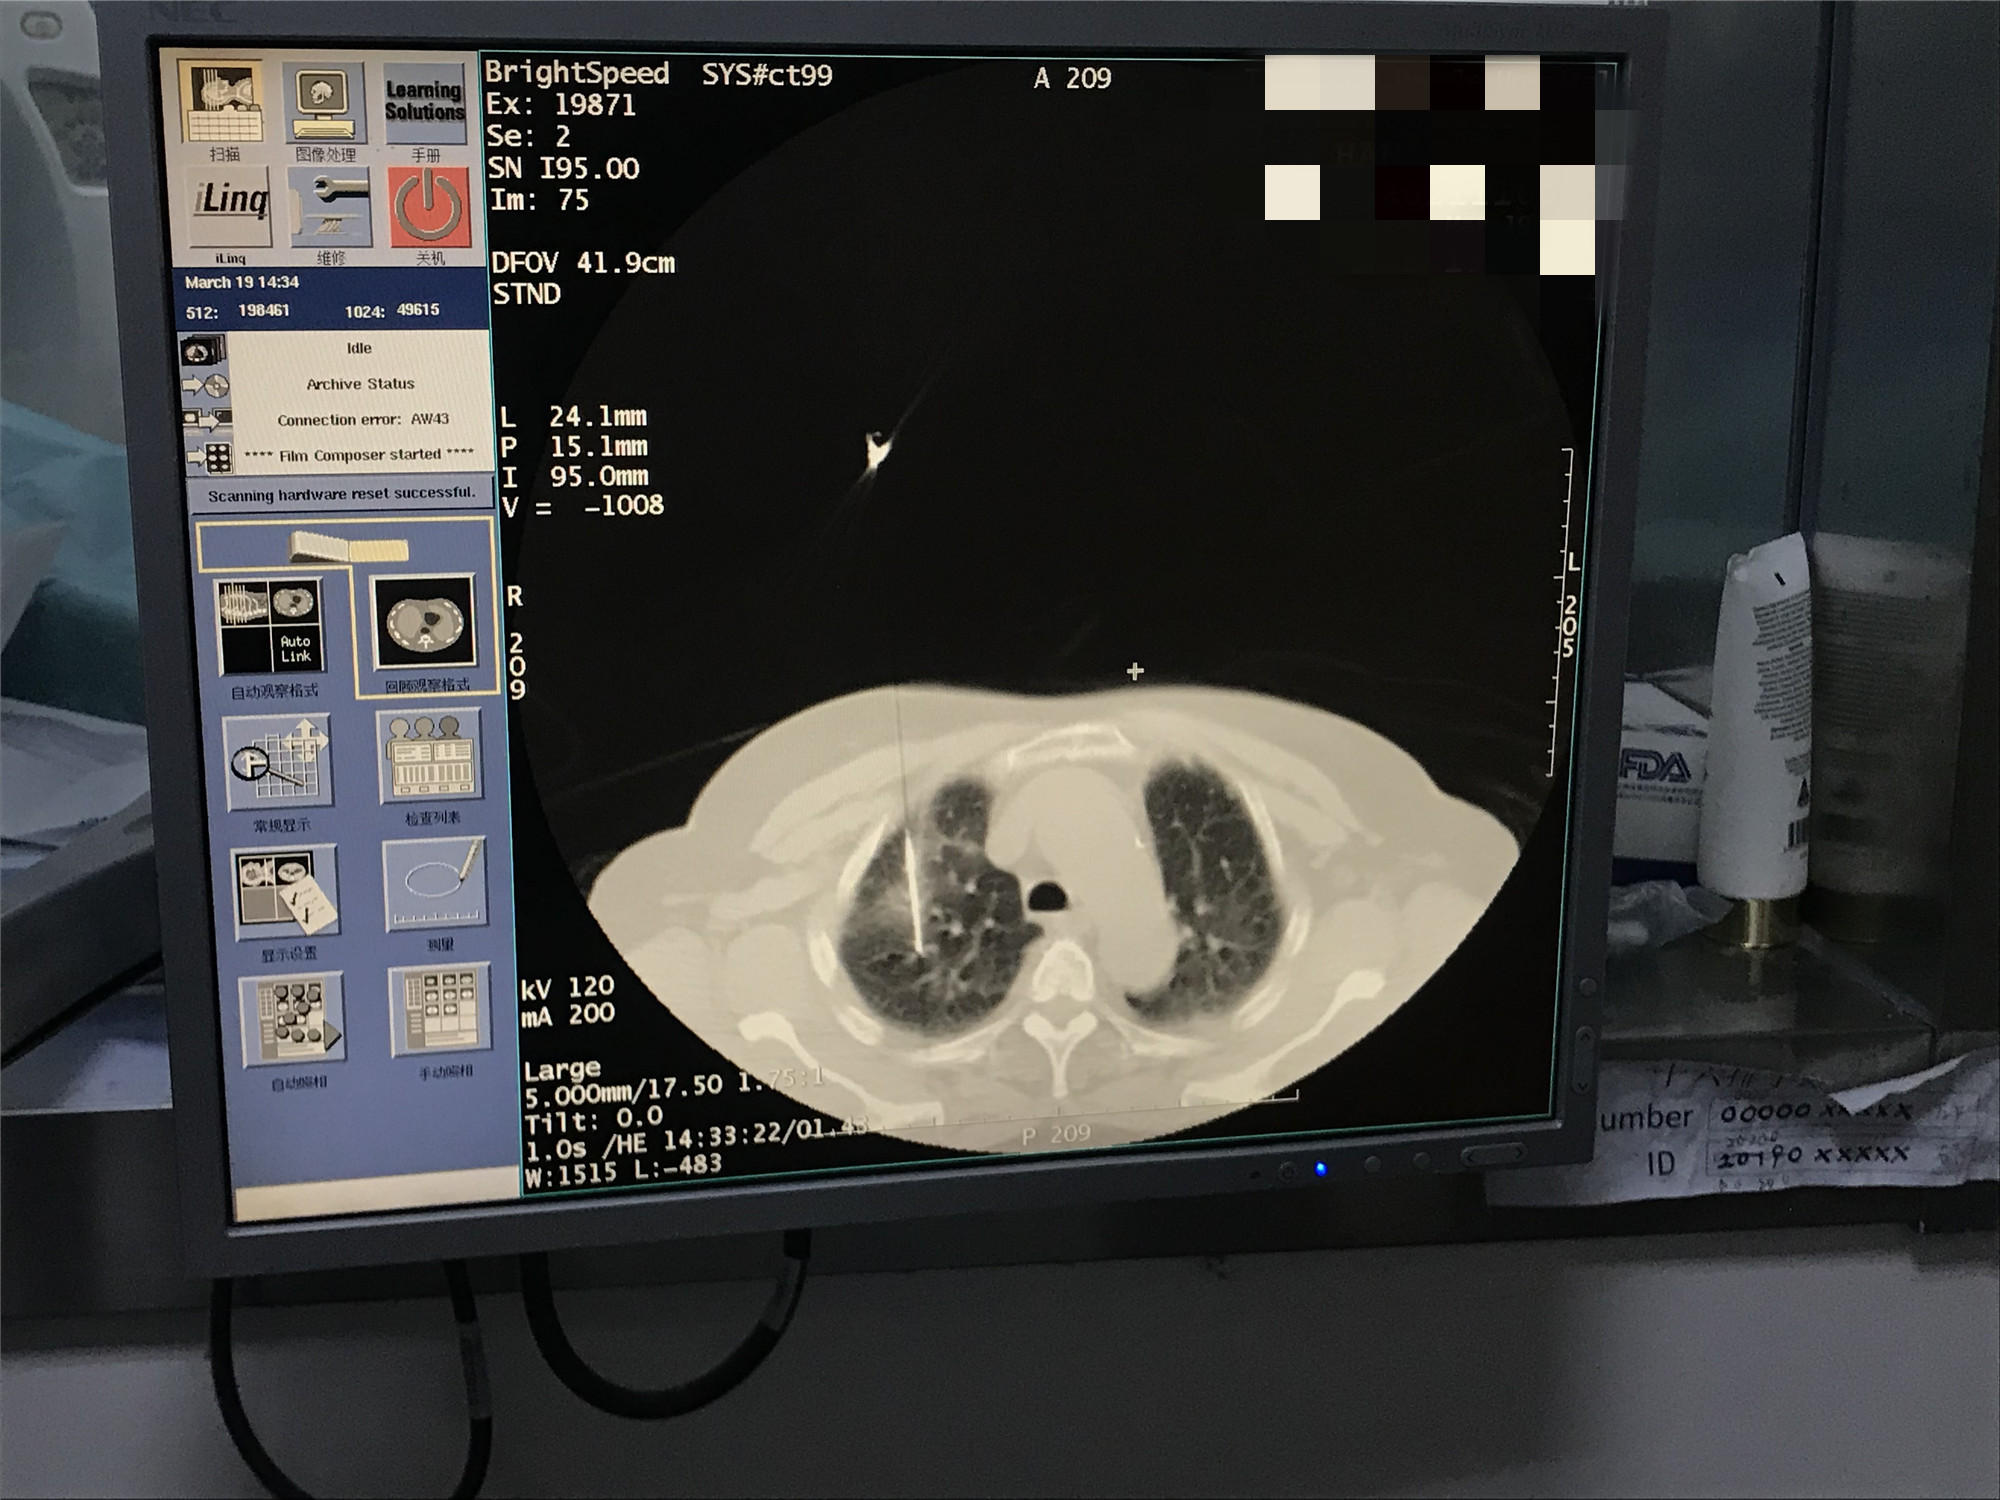

2021年3月份肺部氩氦刀手术